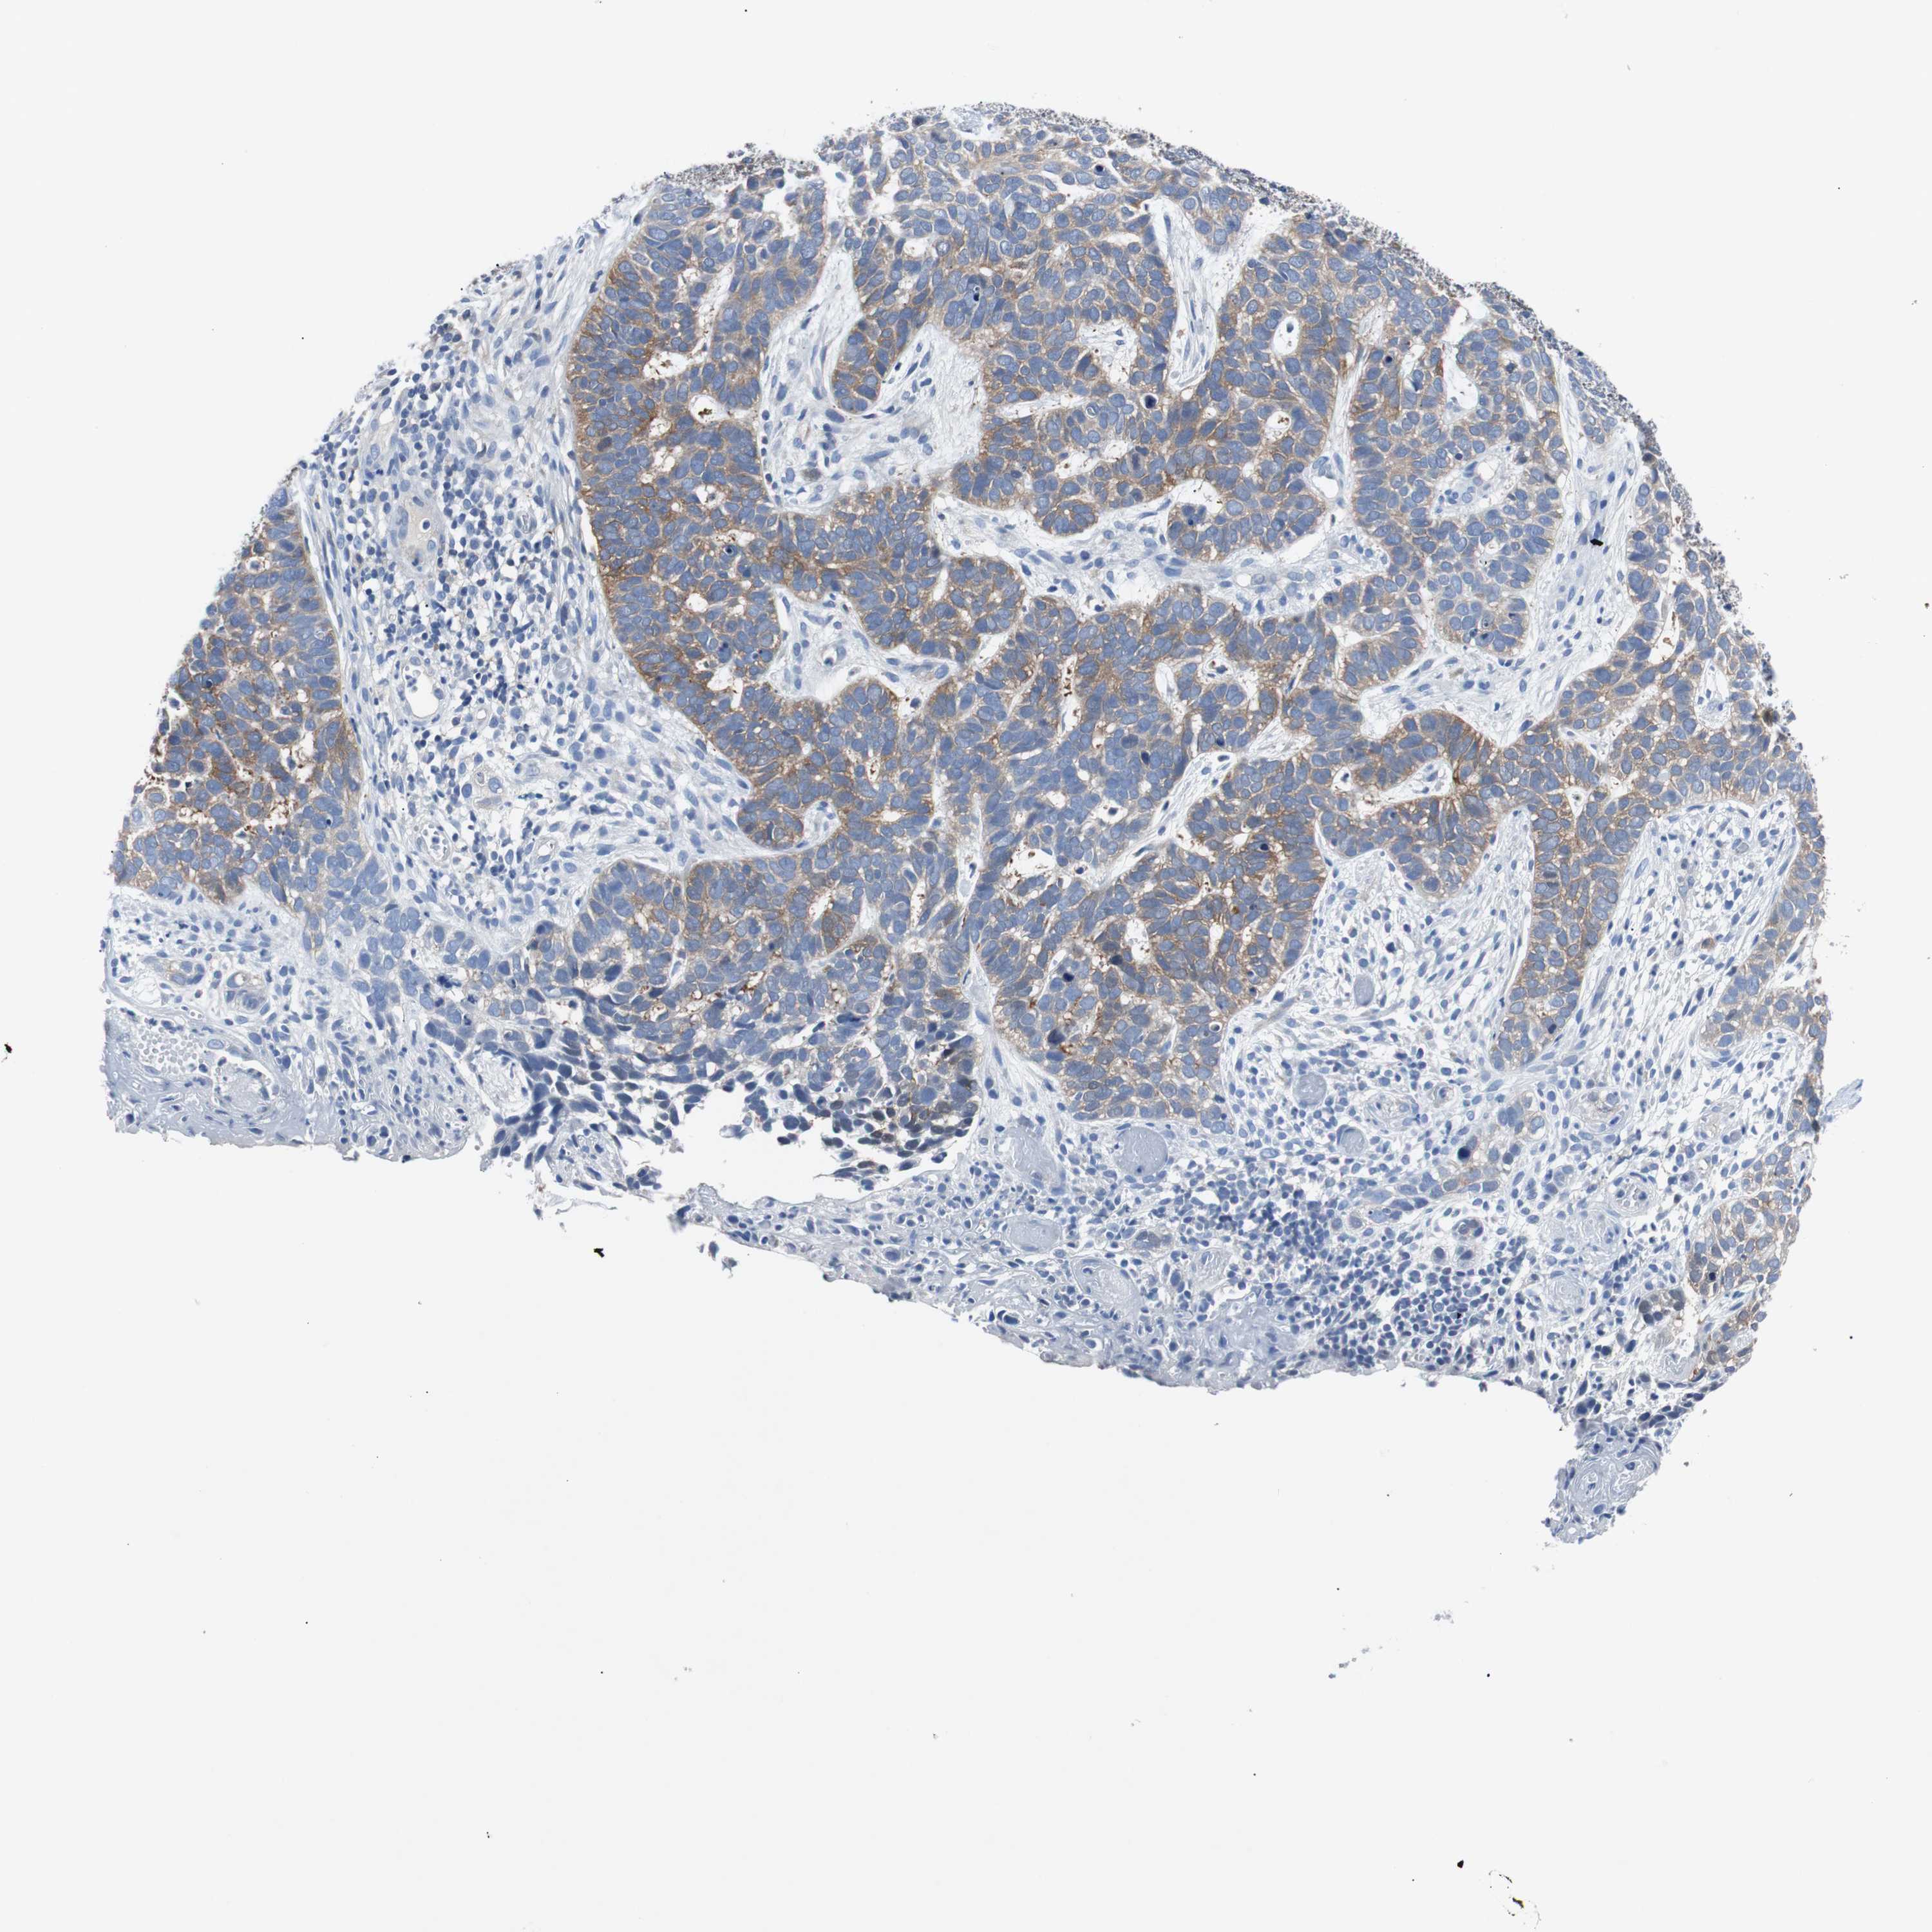

CANCER SKIN CANCER Show tissue menu

Basal cell and squamous cell cancer

SKIN CANCER - Protein expressioni

A mouse-over function shows sample information and annotation data. Click on an image to view it in a full screen mode. Samples can be filtered based on level of antibody staining by selecting one or several of the following categories: high, medium, low and not detected. The assay and annotation is described here.

Each image is clickable and will lead to virtual microscopy that enables deeper exploration of all samples and also displays staining intensity scores, fraction scores and subcellular localization as well as patient and tissue information for each sample.

Antibody CAB007818

Staining

High

Strong

Moderate

>75%

75%-25%

Location

Cytoplasmic/membranous

Squamous cell carcinoma, NOS